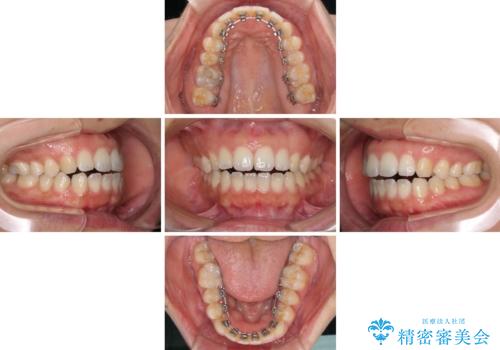

全く目立たないワイヤー矯正 上下リンガル矯正

- フルリンガル

- 上下の前歯のでこぼこを気にして来院された患者様です。

結婚式が近いこともあり、全く目立たない裏側矯正により口元を整えることとしました。

下顎が左側にずれているため、裏側矯正ということもあり咬み合わせを整えるのに時間がかかってしまいました。